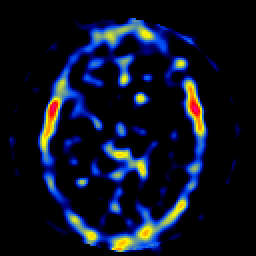

SPECT TL Study #8 -- Slice #27